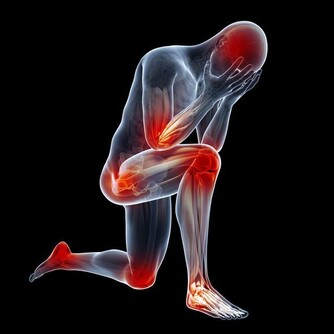

過敏表現常在接觸過敏原半小時至數小時後出現。一般表現如下:煩躁、心慌、胸悶、咽部不適、視物模糊、疲勞、易激惹、緊張、自控力下降、忍耐力下降、情緒失控、皮膚潮紅、紫癜、皮疹、耳道濕潤、鼻塞、鼻涕、鼻塞、噴嚏、眼瞼浮腫、腹痛、腹瀉、多汗、咳嗽,哮喘,呼吸淺快、血壓降低、關節冷痛等等。可見於多種過敏性疾病(如過敏性哮喘、咳嗽、紫癜、皮炎、鼻炎)、一些易激綜合徵(比如腸易激,還有情緒易激等等)、濕疹、痛經、咽炎等等。

過敏體質的本質都是陽虛的,甚或有陽虛肝鬱。這一類人都是敏感體質,包括對自身及外界物質、環境、狀況、境遇都不能很好的適應,從而出現癢、痛、瘡等等表現。我們不能不想到一句經典的詞語“諸痛癢瘡,皆屬於心”。其一般表現如下:怕冷、怕熱、手足發涼、自汗、煩躁、心慌、胸悶、咽部不適、視物模糊、入睡困難或嗜睡、易疲勞、易激惹、緊張、驚悸、自控力下降、忍耐力下降、情緒失控、失眠、多夢、皮膚潮紅、皮疹、耳道濕潤、鼻塞、鼻涕、鼻塞、噴嚏、眼瞼浮腫、腹痛、腹瀉、腹脹、納差、脅痛、易感、咳嗽、咳吐涎沫、哮喘、小便頻多、舌淡體大或有齒痕、脈象沉細或結代等。